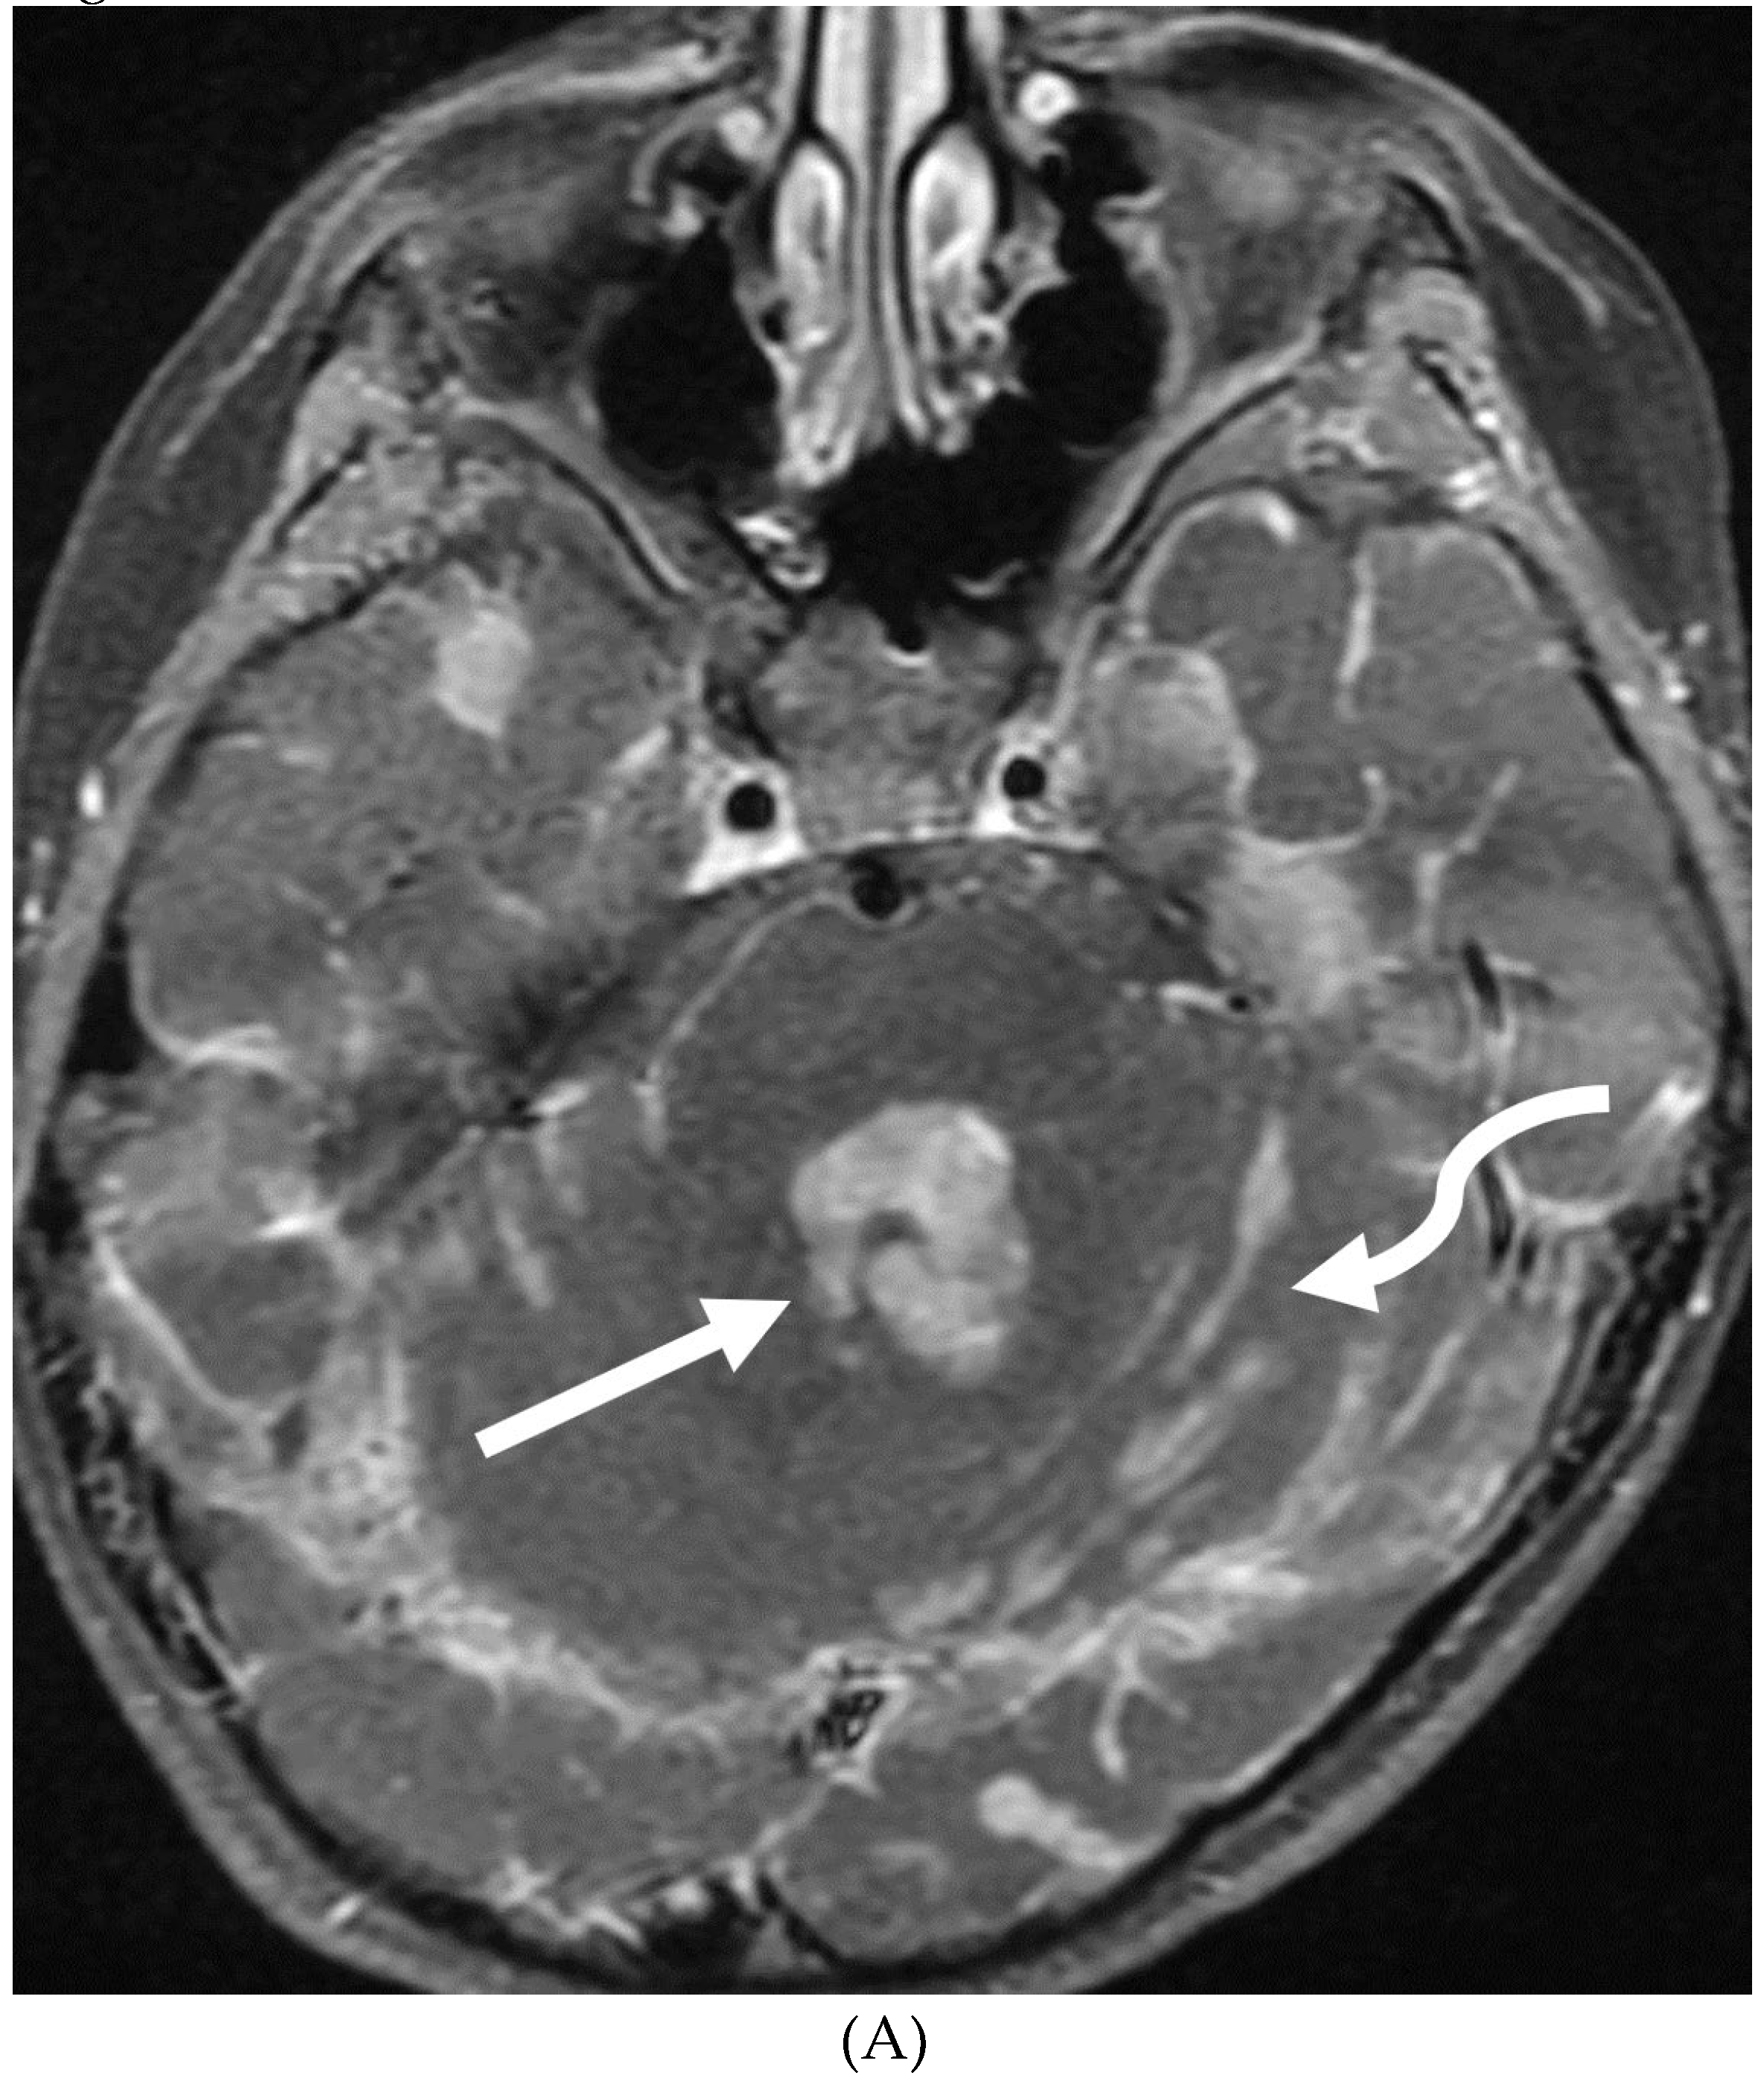

GUILLAIN BARRE SYNDROME

- Alkan O, Yildirim T, Tokmak N, Tan M. Spinal MRI findings of guillain-barré syndrome. J Radiol Case Rep. 2009;3(3):25-8. Epub 2009 Mar 1. PMID: 22470650; PMCID: PMC3303301. [CrossRef]

- Zuccoli G, Panigrahy A, Bailey A, Fitz C. Redefining the Guillain-Barré spectrum in children: neuroimaging findings of cranial nerve involvement. AJNR Am J Neuroradiol. 2011 Apr;32(4):639-42. Epub 2011 Feb 3. PMID: 21292802; PMCID: PMC7965877. [CrossRef]

- Yikilmaz A, Doganay S, Gumus H, Per H, Kumandas S, Coskun A. Magnetic resonance imaging of childhood Guillain-Barre syndrome. Childs Nerv Syst. 2010 Aug;26(8):1103-8. Epub 2010 Jun 17. PMID: 20556395. [CrossRef]

- Byun WM, Park WK, Park BH, Ahn SH, Hwang MS, Chang JC. Guillain-Barré syndrome: MR imaging findings of the spine in eight patients. Radiology. 1998 Jul;208(1):137-41. PMID: 9646804. [CrossRef]